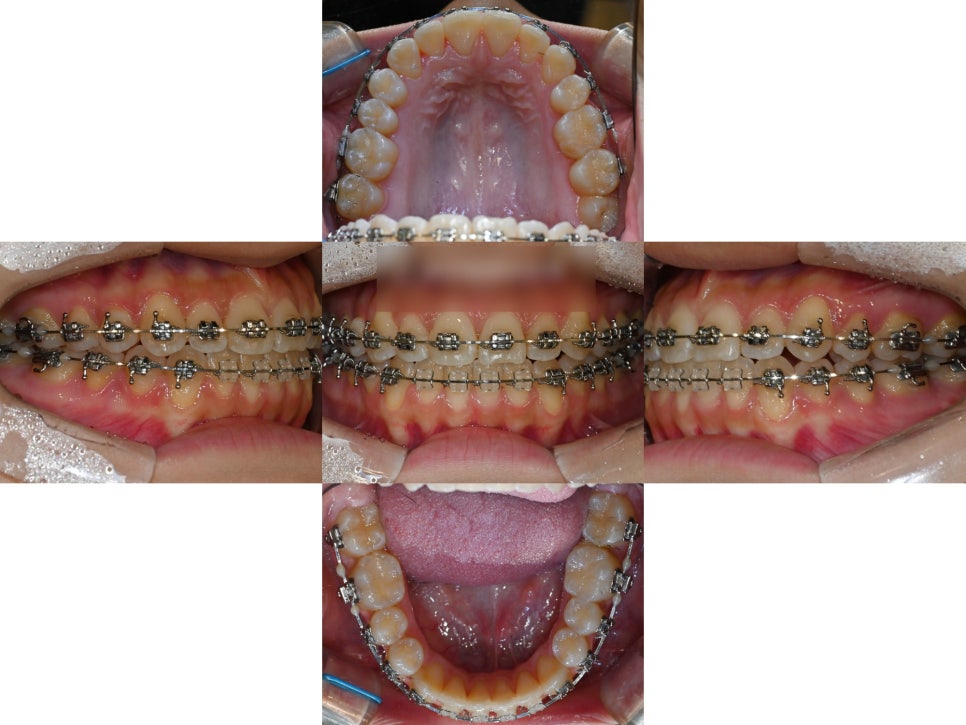

다음은 실제 치료과정입니다.

먼저, 윗니가 아랫니를 충분히 덮어줄 수 있도록

위턱을 확장시키는 작업을 진행했습니다.

(MARPE 장치 사용)

어느정도 위턱이 확장되면서

공간이 조금씩 생기기 시작할때,

치아들을 가지런하게 배열하며

오른쪽 결손부위로 인해 틀어진 정중선까지

최대한 일치시키는 이동계획을 잡았습니다.

상악 확장이 잘 이루어져

윗니가 아랫니를 덮을 수 있는

상태가 되었습니다.

그러나 여전히 교합은 불안정합니다.